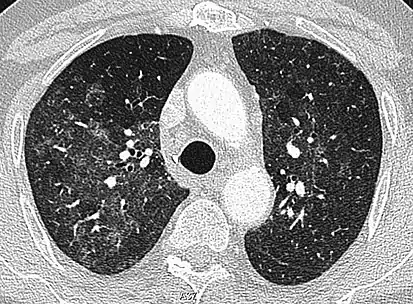

Diffuse

The diffuse pattern typically refers to GGOs in multiple lobes of one or both lungs. Broadly, a diffuse pattern of GGO can be caused by displacement of air with fluid, inflammatory debris, or fibrosis. Cardiogenic pulmonary edema and ARDS are common causes of a fluid-filled lung. Diffuse alveolar hemorrhage is a rarer cause of diffuse GGO seen in some types of vasculitis, autoimmune conditions, and bleeding disorders.[6]

Inflammation and fibrosis can also cause diffuse GGOs. Pneumocystis pneumonia, an infection typically seen in immunocompromised (e.g. patients with AIDS) or immunosuppressed individuals, is a classic cause of diffuse GGOs. Many viral pneumonias and idiopathic interstitial pneumonias can also lead to a diffuse GGO pattern. Radiation pneumonitis, a side effect of pulmonary radiation therapy, can lead to pulmonary fibrosis and diffuse GGOs.[6]